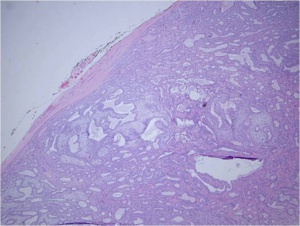

The gross tumor is typically has a pseudocapsule of surrounding tissue, without invasion. (see figure 1).Histologic sections reveal ductal epithelial cells with surrounding myoepithelial cells. The cells have benign cytology (see figures 2 and 3). The exact cause of PALG is unknown. Genetic rearrangements, such as chromosomal translocations involving 8q12 target the PLAG1 gene, may contribute to the pathophysiology of PALG. Alterations in this developmentally regulated zinc finger gene can lead to deregulation of target genes, including IGF2, and is likely to play a major role in the genesis of pleomorphic adenomas.[4]